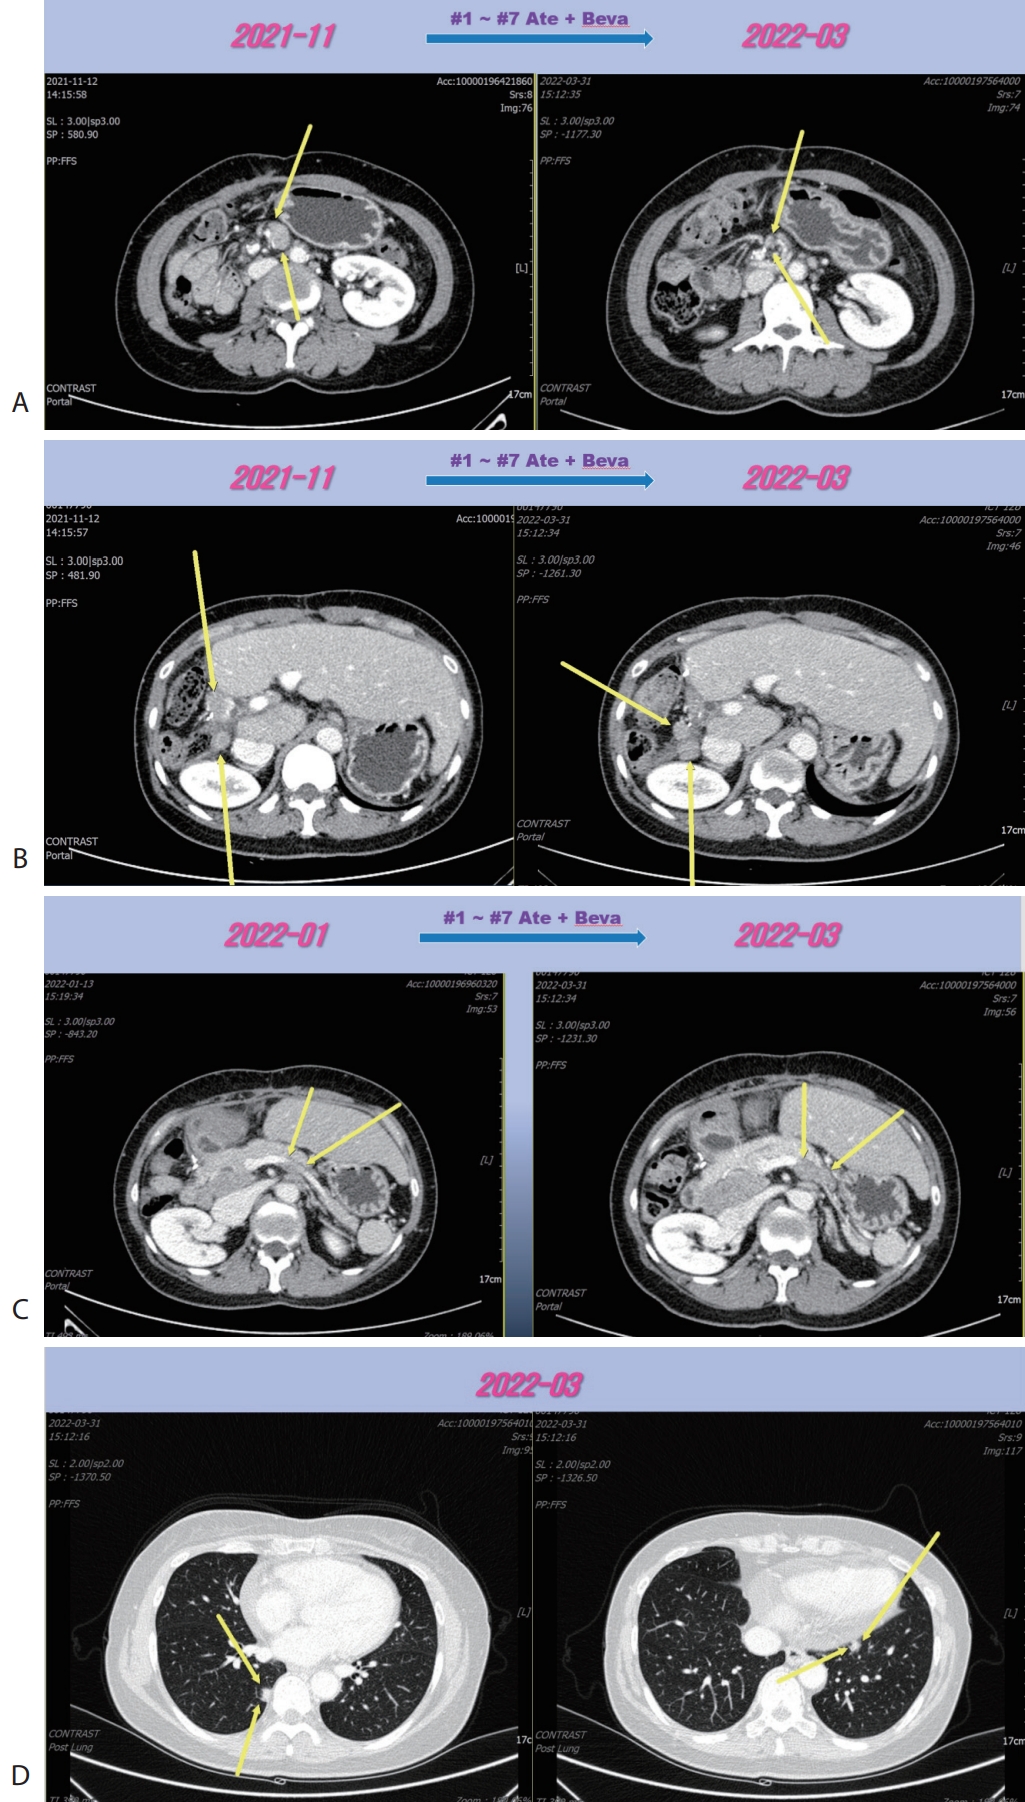

A 56-year-old woman with a multiple peritoneal and LN metastasis of HCC was admitted to our hospital from a nearby cancer center in November 2021. She already received right hemi-hepatectomy for initial HCC in 2018 and radiofrequency ablation for recurred tumor in 2019 and multiple times of excision for peritoneal & LN metastasis in 2021. However the metastasis was aggravated despite of previous several times of metastasectomy. Computed tomography (CT) revealed multiple LN & peritoneal metastasis (maximum diameter 6 cm) (

® 15 mg/kg per dose; Genentech, South San Francisco, CA, USA) were administered every 3 weeks on the same day. Following the seven cycles of Ate+Beva, liver CT scan revealed several peritoneal and LN metastasis were decreased compared to the prior CT scan (

Fig. 2A). However prerenal and peripancreatic LN metastasis were increased, moreover new onset lung metastasis was happened (

Fig. 2B–

D). We concluded this mixed response as an oligo-progression and treated the patient with same systemic therapy (Ate+Beva) combining radiotherapy (RT) for prerenal LN metastasis (45 Gray/25 fraction). In follow-up CT scan that was conducted 6 months after commencing Ate+Beva plus RT, abdominal increasing LN metastasis previously was markedly shrinked (

Figure 1.Liver CT scan. Huge portocaval lymph node (6 cm sized) metastasis was observed. CT, computed tomography.

Figure 2.Liver CT scan (A–C) and chest CT scan (D) after seven cycles of 1st line Ate+Beva therapy. Almost peritoneal metastasis were shrinked (A). However prerenal (B) and peripancreatic (C) lymph node metastasis were increased and new onset lung metastasis was detected (D). CT, computed tomography; Ate+Beva, atezolizumab plus bevacizumab.